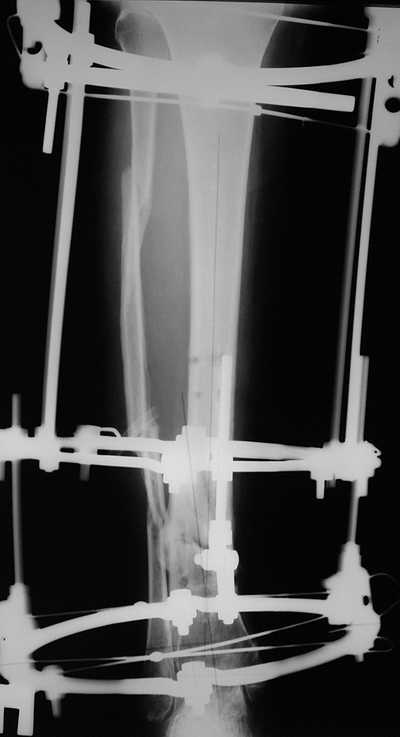

Женщина 46 лет, неудачно лечившаяся по поводу перелома голени в нижней 1\3 сначала в гипсе, поступила через 6 месяцев после остеосинтеза пластиной (рис 1). Имелась деформация в нижней 1\3 голени: варус, антекурвация, наружная ротация, два свища. Удалена пластина, дебридмент мягких тканей,

остеотомия м\б кости, аппарат Илизарова. По рентгенограммам в двух проекциях произведено планирование устранения смещений (рис 2 и 3), между вторым и третьим кольцом установлены 6 телескопических дистракторов Гесапода, данные введены в программу, и далее втечение 10 дней больная подкручивала телескопы согласно выданной компьютером инструкции. По завершению репозиции гексаподные телескопы обратно заменены на обычные штанги от аппарата Илизарова (рис 4 и 5). Еще через две недели забит гвоздь (рис 6, контроль

через 4 месяца).